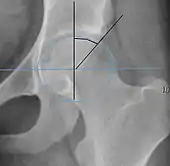

Radiograph of a pincer type impingement.

Projectional radiography ("X-ray")is often considered first line for FAI.[10] Anterior-posterior pelvis and a lateral image of the hip in question should be attained.[10] A 45-degree Dunn view is also recommended.[10][19]

Measurements of impingement on X-ray.[notes 1][20]

MeasurementImageTargetNormal value

Crossing ratio Percentage of acetabular walls crossing. Normal acetabulum is oriented in anteversion. Its value ranges from 15 to 20° in the equatorial plane of the acetabulum and decreases gradually towards the acetabular roof, where normal values range from 0 to 5°. Retroversion of the upper part of the acetabulum has been related with pincer type impingement. In radiography the presence of a "crossover sign" is produced when the posterior wall of the acetabulum crosses the anterior wall before reaching the acetabular roof. It is a sign of acetabular retroversion and it has been linked with overcoverage and pincer impingement. Nevertheless, this sign has been described in 6% of the normal population. Therefore, more important than its presence is the percentage of crossing. <20%

• Higher is significant crossing